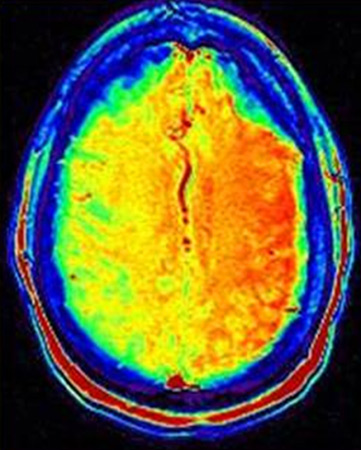

[Figure caption and citation for the preceding image starts]: Imagen de etiquetado de espín arterial de IRM en que se observa la hipoperfusión de gran extensión en el hemisferio cerebral derecho. Existe una discordancia clara entre difusión y perfusiónDe la colección personal de Eric E. Smith; usado con autorización [Citation ends].